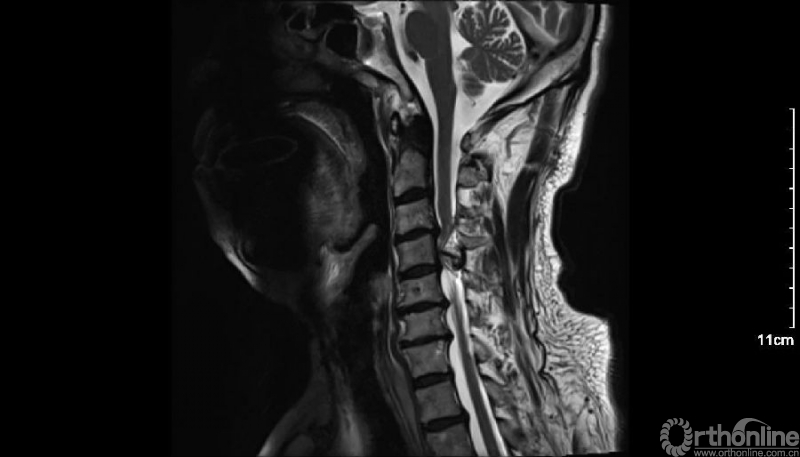

患者男性,68岁,主因四肢麻木、无力、走路不稳5年,加重20天入院。患者诉20年前有过颈椎外伤史。

入院查体患者四肢肌张力高,双侧hoffman阳性。CT及MRI检查提示C4/5左侧关节突内缘有一巨大骨块(15mm*16mm),相应节段椎管严重狭窄。椎管内骨块的前端还有一游离骨块。

影像学资料